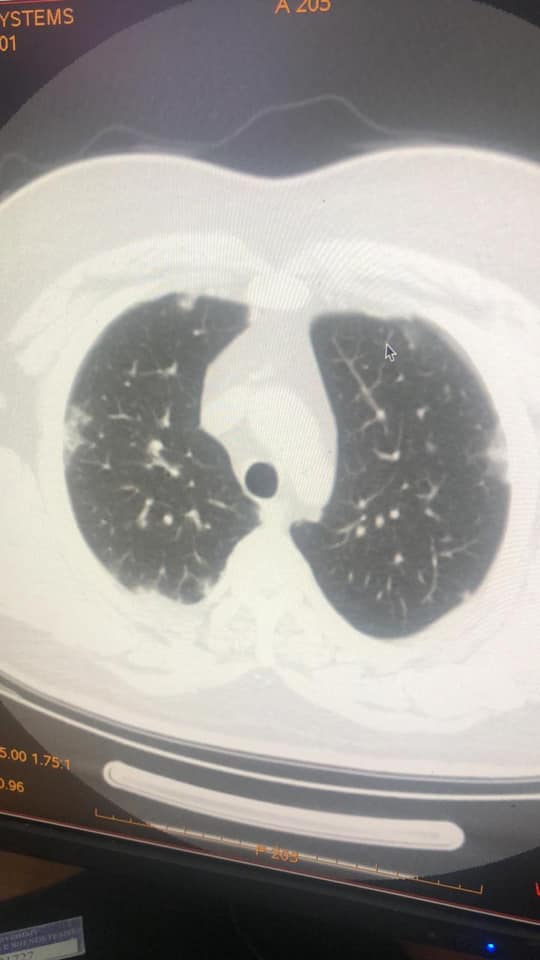

Mjeku Gëzim Xhepa publikon imazhet: Koronavirusi ka qenë në Shqipëri që prej 15 janarit

Koronavirusi ka qenë prezent në Shqipëri që prej datës 15-20 janar. Kështu pretendon mjeku Gëzim Xhepa referuar disa imazheve pulmore të pacientëve që kanë qenë të shtruar në Infektiv në këto data.

Imazhet e publikuara nga mjeku i njohur Gëzim Xhepa, janë evidentuar nga kolegu i tij imazherist Renato Osmani.

Xhepa ka publikuar fotot që tregojnë praninë e koronavirusit që në mesin e muajit janar.

IMAZHET E JANARIT QË FLASIN PËR PREZENCËN E COVID-19 NË SHQIPËRI QË NË KËTË PERIUDHË

Sot, falë mikut dhe kolegut tim të nderuar Dr. Renato Osmani…, imazhëristit që ishte i pari, që javën e parë pas zbulimit të të ashtuquajturit rast 0, identifikoi fizionominë dhe identitetin imazhërik pulmonar të COVID-19… dhe potencën e ekzaminimit CT ndër ekzaminimet e skemës bazë për diagnostikim dhe përcaktim prognose…, mu ofruan imazhe të pakundërshtueshme të prezencës së COVID-19 në datat 15 – 20 janar, në disa raste në Infektiv…!!!

Faleminderit Dr. Renato…, jo vetëm për menaxhimin pa panik, por me vigjilencë të situatës së karantinës, nëpërmjet centarlizimit dhe koordinimit nacional imazhërik për suspektim sa më të hershëm të sëmundjes dhe prevenimin e kaosit, që mund të kish shkaktuar strategjia e gabuar e numrit 127…, por edhe për ndihmën që po jep për Komitetin Teknik për konfuzionin në pritjen e pikut epidemiologjik…!!! Po ju ofroj pamjet imazhërike të pesë rasteve, duke ju kujtuar që janë pronë intelektuale e Dr. Renato Osmani dhe i publikoj me aprovimin e tij, duke mbrojtur të drejtën e tij të aitorit…!!!